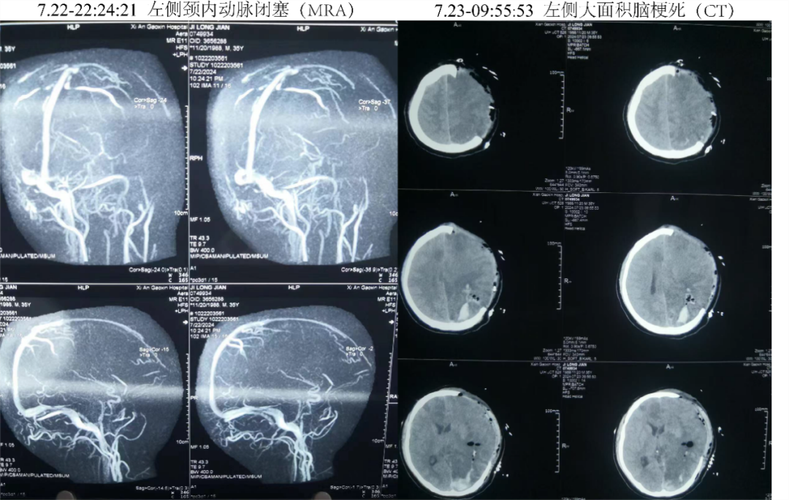

CT检查如何诊断术后出血?(影像学表现)

CT是诊断脑出血的“金标准”,快速、准确,对于脑梗术后患者,CT检查主要看以下几点:

典型CT表现:高密度影

- 急性期出血(数小时内): 在CT图像上,新鲜的出血表现为边界清晰的、密度增高的区域(白色或亮白色),这与脑梗死的低密度(黑色或暗色)影形成鲜明对比。

- 位置: 血肿可以位于:

- 手术区域(原发): 最常见,即在开颅的部位或血肿清除的部位再次出现新的高密度影。

- 远离手术区域(继发): 可能是由于再灌注损伤导致梗死区内部出血,或因高血压导致其他部位血管破裂。